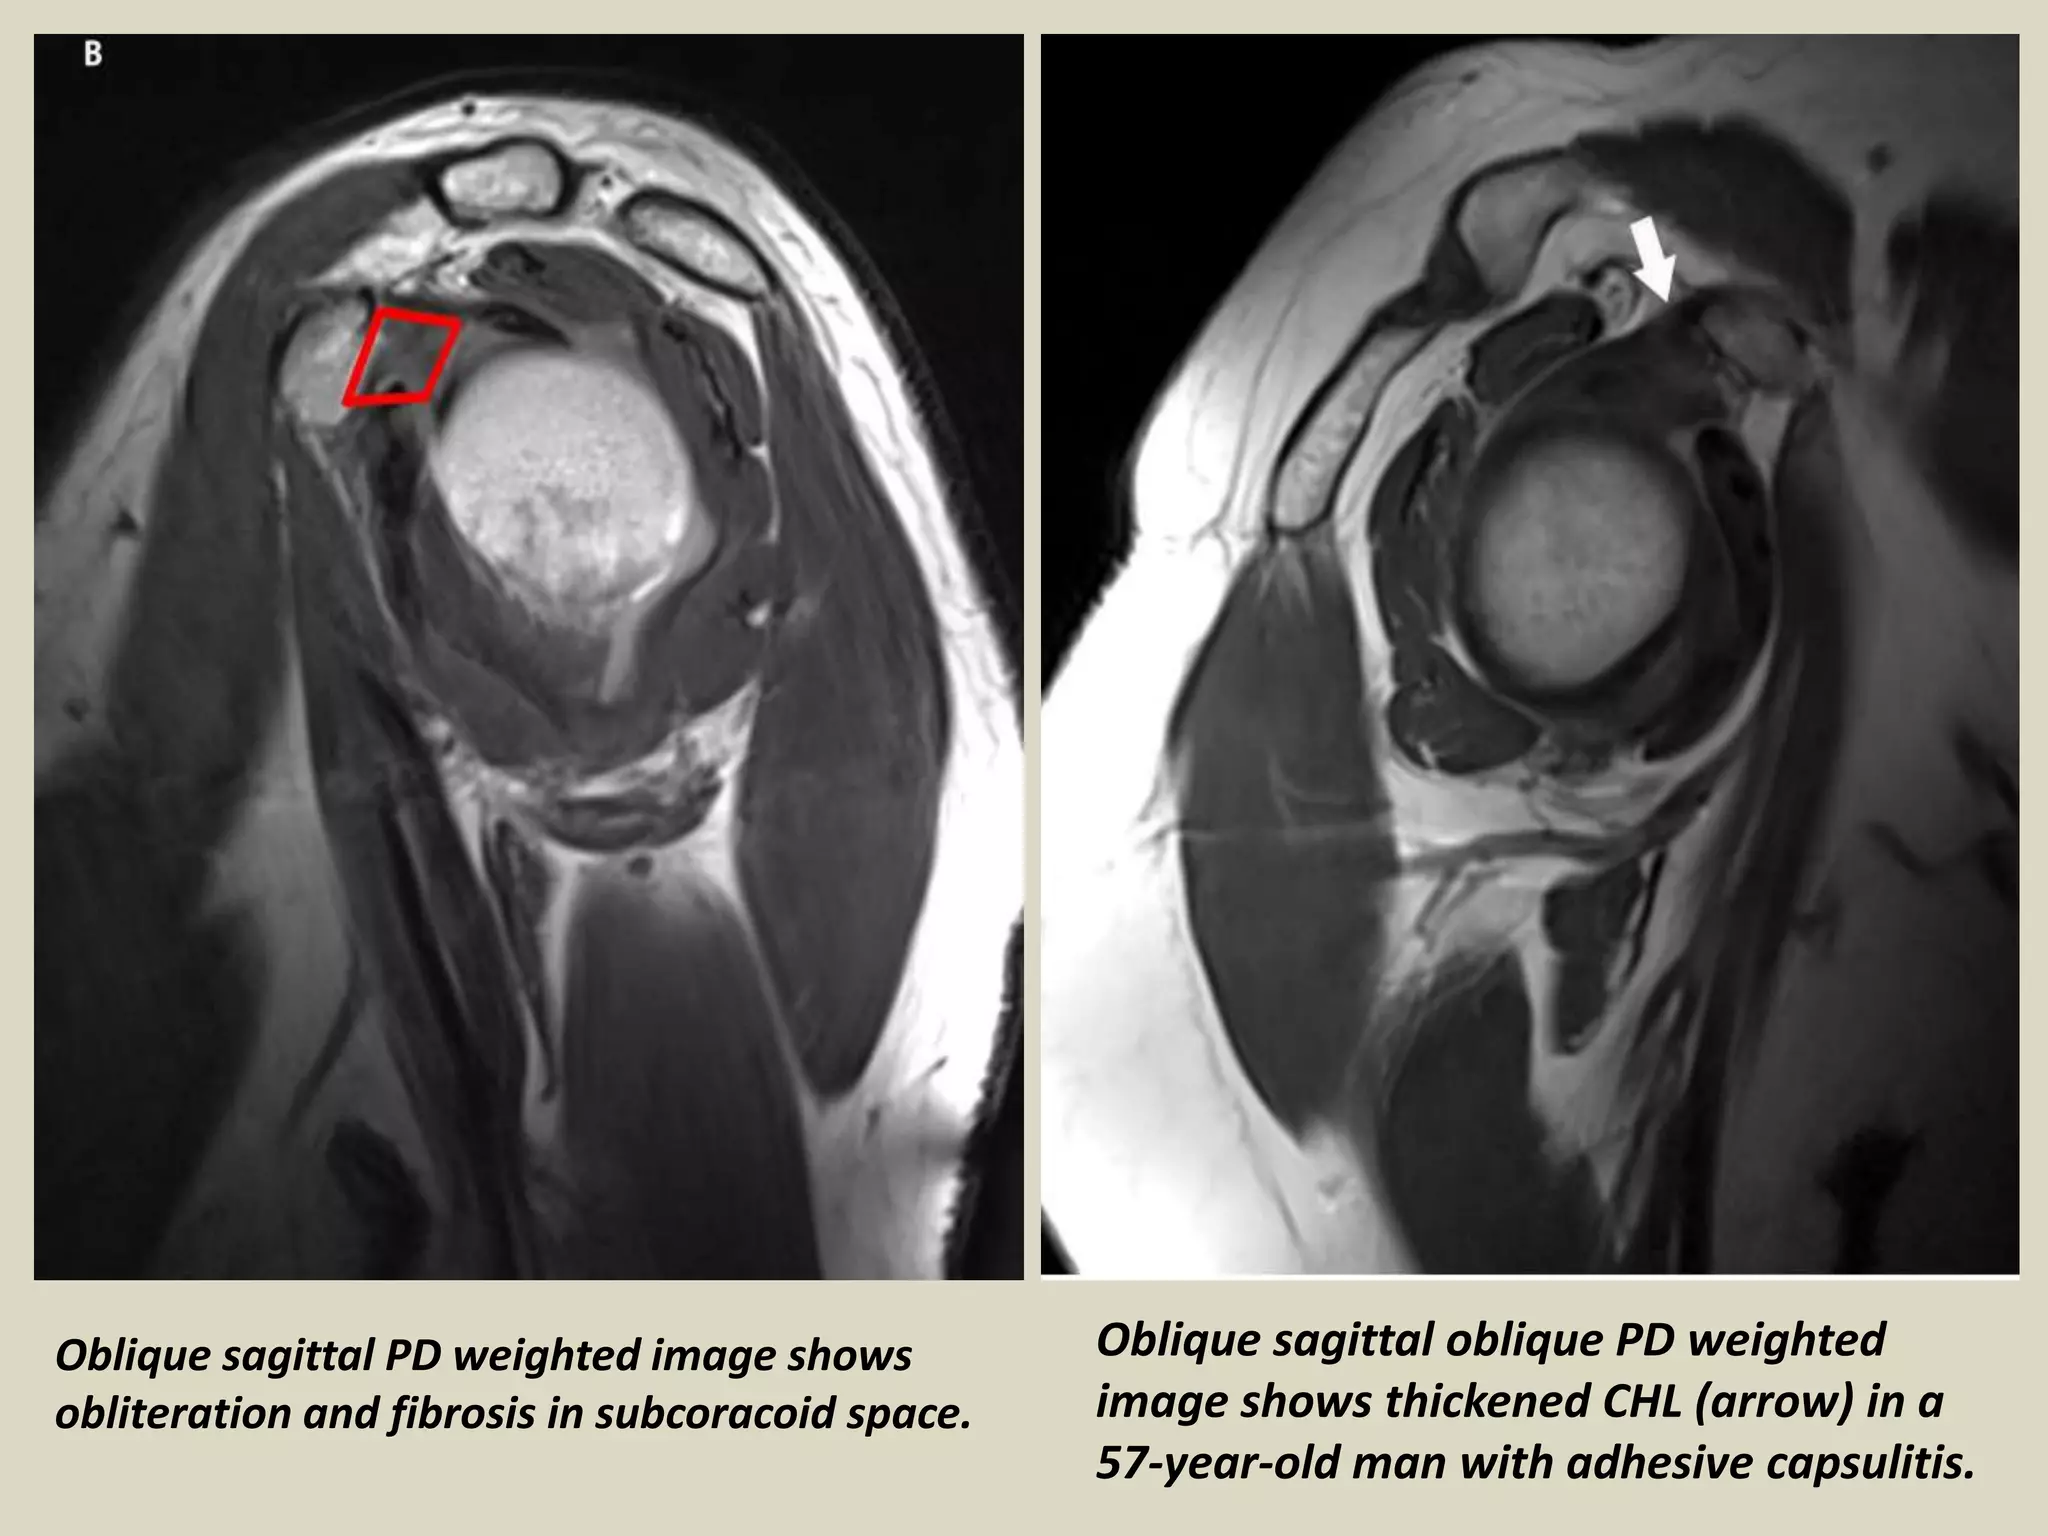

Adhesive Capsulitis Imaging . Diagnosing adhesive capsulitis is primarily determined by history and physical examination, but imaging studies can be used to rule out underlying pathology. This narrative review provides an updated analysis of the current concepts on the role of imaging modalities in patients with. Diagnosis of adhesive capsulitis may be suggested on imaging by several characteristic findings, mri being the imaging modality of choice. Adhesive capsulitis, commonly referred to as frozen shoulder, is a debilitating condition characterized by progressive pain and limited. Radiographs are typically normal with adhesive capsulitis but can identify osseous abnormalities, such as glenohumeral osteoarthritis. Adhesive capsulitis (ac) of the shoulder has been a diagnosis of exclusion on sonography due to lack of specific diagnostic. Adhesive capsulitis (also known as frozen shoulder) is a condition of the shoulder characterized by functional loss of both passive and active shoulder motion commonly. Thickening of the chl, axillary. Although imaging is not necessary to make the diagnosis, a finding of coracohumeral ligament thickening on noncontrast magnetic resonance imaging.